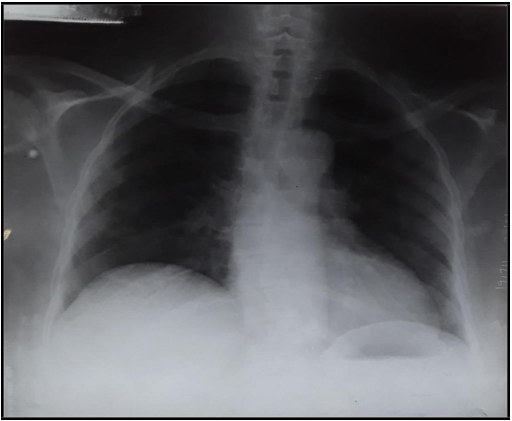

Is Tocilizumab a game-changer in managing severe COVID-19? A case report from Ile-Ife, Nigeria.